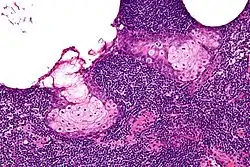

High magnification micrograph of a sebaceous lymphadenoma. H&E stain.

Sebaceous lymphadenoma is a benign tumour of the salivary gland.[1]

Sebaceous lymphadenoma is a tissue diagnosis, e.g. salivary gland biopsy.